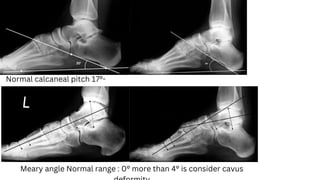

Normal calcaneal pitch 17°-

32°

Meary angle Normal range : 0° more than 4° is consider cavus

Normal Talocalcaneal angle:

25° - 45°, less than 20° is

consider cavus